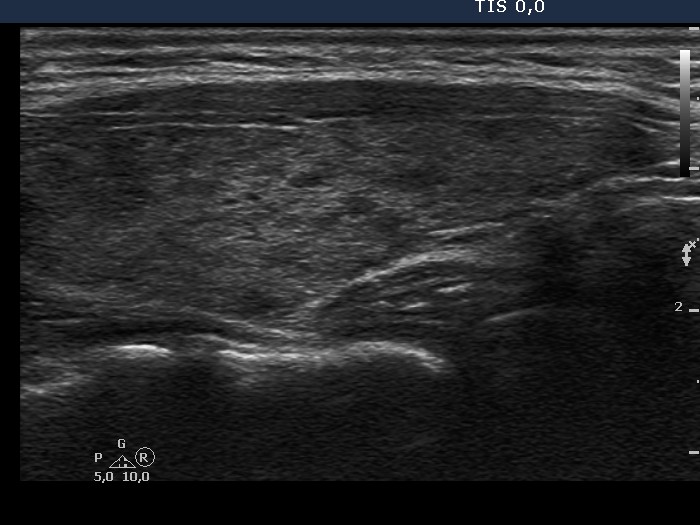

Graves' disease - Case 25. (ultrasonographic picture 5)

Left lobe, longitudinal scan.